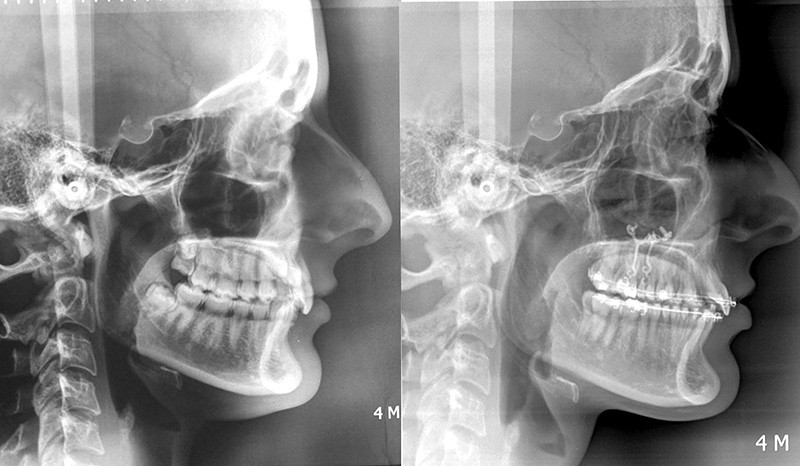

Aline se présente à la consultation pour une demande esthétique concernant ses deux canines lactéales qu’elle trouve trop petites et trop blanches (fig. 1a). Elle présente une classe II squelettique légère sur un schéma méso-divergent. D’un point de vue dentaire, une supraclusion est associée à une classe II d’Angle complète à gauche et de 4 mm à droite. Les canines maxillaires sont incluses (une vestibulaire et une palatine), avec persistance de leurs dents lactéales sur l’arcade (fig. 1b-h).

Un protocole orthodontico-chirurgical avec avancée mandibulaire est envisagé pour assurer un bon soutien labial, mais cette option est refusée par la patiente qui craint un visage trop carré. Concernant l’inclusion des canines maxillaires définitives, plusieurs thérapeutiques sont envisageables : 53, 63, 13, 23, ou 53, 63, 14, 24 peuvent être extraites, avec pour conséquence une classe II thérapeutique au niveau des molaires en fin de traitement. Cependant, la patiente souhaite mettre en place ses canines incluses pour conserver tout son capital dentaire et rétablir un idéal fonctionnel et esthétique au niveau des dents antérieures (fig. 2).